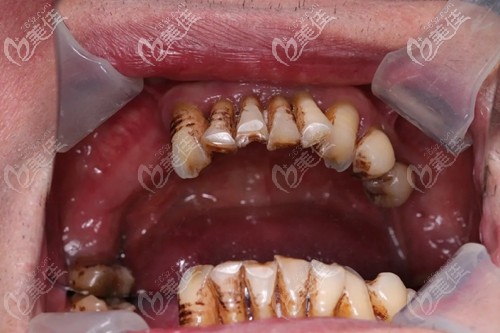

陳先生今年52歲,來(lái)院檢查發(fā)現(xiàn)全口牙齒松動(dòng),脫落多顆,針對(duì)這種情況經(jīng)驗(yàn)豐富的曾院長(zhǎng)為他制定了上8下8,全口種植的方案。

陳先生術(shù)前口內(nèi)照

就診前陳先生拍的CT,難看出全口沒(méi)剩幾顆好牙了,牙齒松動(dòng)明顯、殘根斷齒,多顆牙缺失,年無(wú)法正常咀嚼,真的非常痛苦,所以針對(duì)他的情況選擇全口種植效果會(huì)更好。

據(jù)曾院長(zhǎng)描述,陳先生的口腔情況不容樂(lè)觀,需要解決的問(wèn)題很多:由于牙齒陸續(xù)脫落,牙槽骨吸收情況不一樣,導(dǎo)致骨面凹凸不平,還有一些位置出現(xiàn)了缺骨。

在傳統(tǒng)種植領(lǐng)域,像這樣骨質(zhì)情況的種植手術(shù)受到很大的限制,一方面要大量植骨,增加了種植失敗的風(fēng)險(xiǎn),另一方面加倍延長(zhǎng)了種植戴牙時(shí)間,所以這臺(tái)種植牙手術(shù)對(duì)于醫(yī)生的技術(shù)和儀器設(shè)備都有很高的要求。